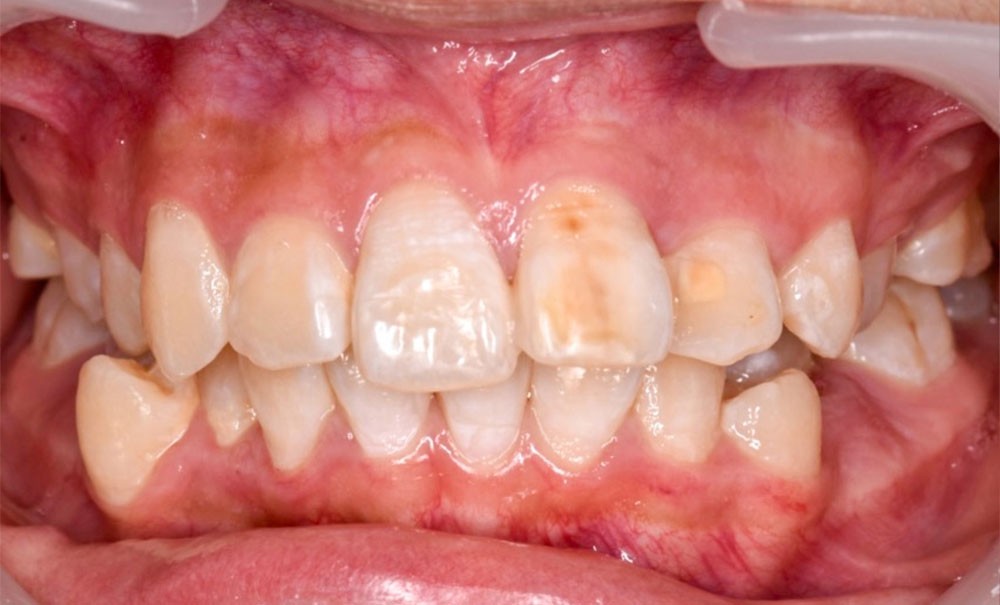

Par ailleurs, le rendu esthétique final du sourire reste marqué par une légère dyschromie entre les 11 et 21. Cela s’explique à la fois par la teinte plus saturée de la canine stratifiée, mais aussi par la discrète fluorose — visible en début de traitement sous forme de stries blanchâtres sur les incisives maxillaires et mandibulaires. De plus, l’apparition de white spot lesions secondaires au traitement a accentué le contraste chromatique. Un apport de vernis fluoré et une prise en charge par érosion-infiltration des lésions fluorotiques sont prévus afin d’harmoniser les teintes [4].

Enfin, une différence de hauteur gingivale est visible lors du sourire entre les collets de 21 et 11, mais surtout entre les 13 et 24. Un aménagement gingival pourra être proposé ultérieurement, selon les attentes esthétiques.